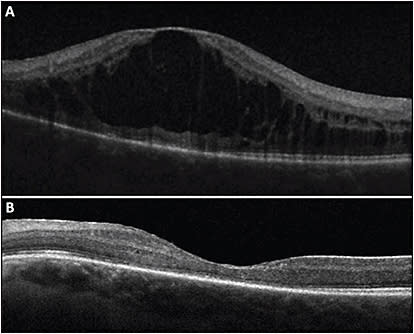

Intravitreal fluocinolone (Iluvien; Alimera Sciences) is a surgically implanted device that releases fluocinolone for 3 years. Data from 2 large cohorts, The Multicenter Uveitis Steroid Treatment Trial (MUST) and Fluocinolone Acetatae Study Group, showed that this implant resulted in resolution of macular edema in 50% of patients by 6 months and an improvement in macular edema in 87% of patients at 2 years, an effect that persisted for 5 years (Figure 3).13,14

The potential benefit of intravitreal fluocinolone, however, must be balanced with the side effects. Ocular hypertension is very common and up to 45% of eyes require incisional glaucoma surgery within 3 years, a 10- to 20-fold increase compared to uveitis patients receiving only systemic treatment. Cataract progression is almost universal, with 90% of phakic eyes requiring surgery (a 3-fold increase compared to the uveitis patients receiving systemic therapy). Both complications primarily occur within the first 2 years.13,14 Finally, there is also a 4.8% incidence of implant dissociation over 6 years, all occurring after 4.8 years as well as rarer surgical complications such as hypotony and endophthalmitis.15 These complications highlight the need for close monitoring of patients after fluocinolone implantation. Bausch + Lomb redesigned the implant to prevent dissociation, however long-term data on the redesigned device is not yet available. Finally, a third intravitreal fluocinolone implant being developed by pSivida (Durasert) is currently being tested in phase 3 trials and may become available soon.